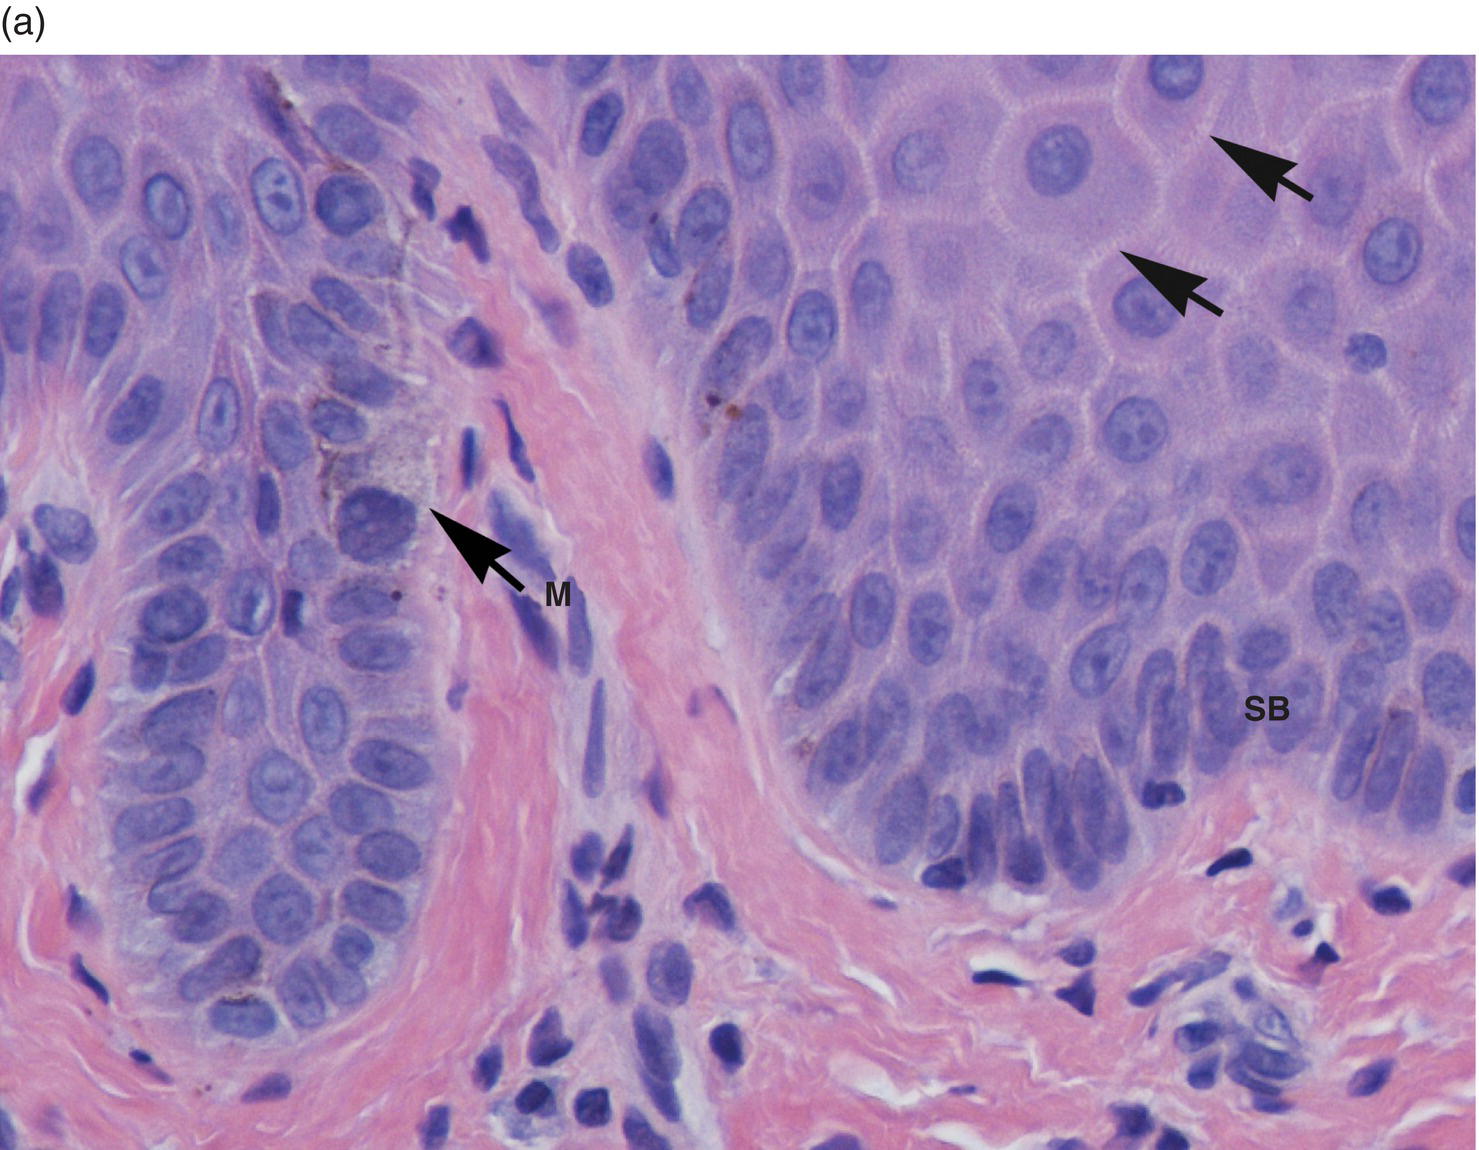

4. What are the structures responsible for intercellular and cell to basement membrane attachment?

Explanation

Desmosomes and hemidesmosomes are specialized structures that help in cell-cell adhesion and attachment to the extracellular matrix. Gap junctions and tight junctions are involved in intercellular communication and barrier formation, respectively. Lysosomes, endosomes, ribosomes, and Golgi apparatus are cellular organelles with different functions unrelated to cell adhesion.